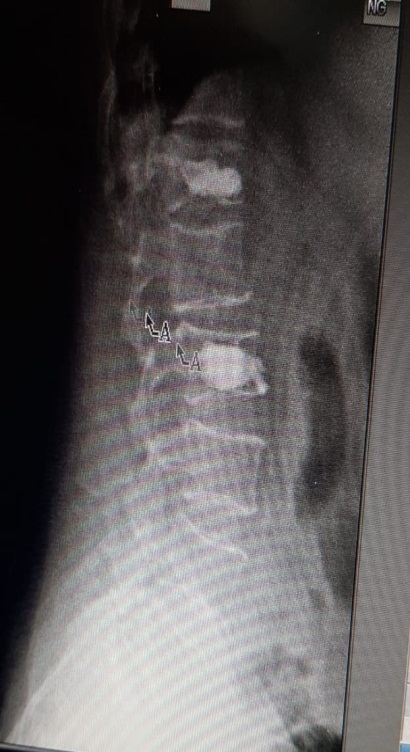

Preop MRI of multiple vertebral collapse

osteoporosis

Postop Xray of the bone operated with kyphoplasty